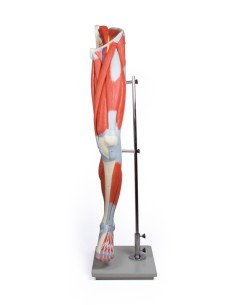

Esplora la nostra collezione dei migliori modelli anatomici degli arti superiori ed inferiori

La nostra esclusiva selezione di modelli anatomici delle estremità, meticolosamente prodotti dai leader del settore 3B Scientific ed Erler Zimmer, offre una rappresentazione fedele e dettagliata delle complesse strutture di mani e piedi. Questi modelli sono fondamentali per chiunque desideri esplorare l’anatomia delle estremità con una precisione senza pari, rendendoli strumenti didattici ideali per l’educazione e la pratica in ortopedia, fisioterapia e medicina dello sport.

Ortopedici, fisioterapisti, studenti di scienze della salute e istituti educativi si affidano ai nostri modelli per le loro esigenze educative e professionali, utilizzandoli per dimostrazioni pratiche e per migliorare la comprensione della meccanica e della funzione delle estremità umane.